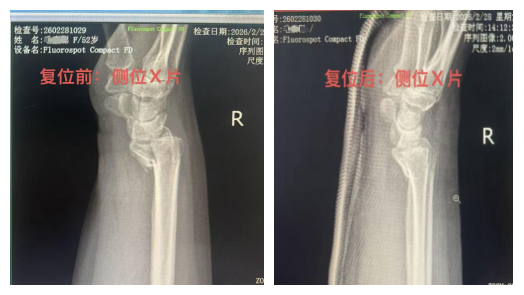

复位前影像显示:桡骨远端骨折端向掌侧明显移位,掌倾角变小,手腕呈现典型“工兵铲样”畸形。

通过患者复位前后影像资料对比,疗效清晰可见:

复位前:骨折端移位显著,关节面塌陷,腕骨排列紊乱;

复位后:骨折端对位、对线良好,关节面恢复平整,腕关节结构回归正常。